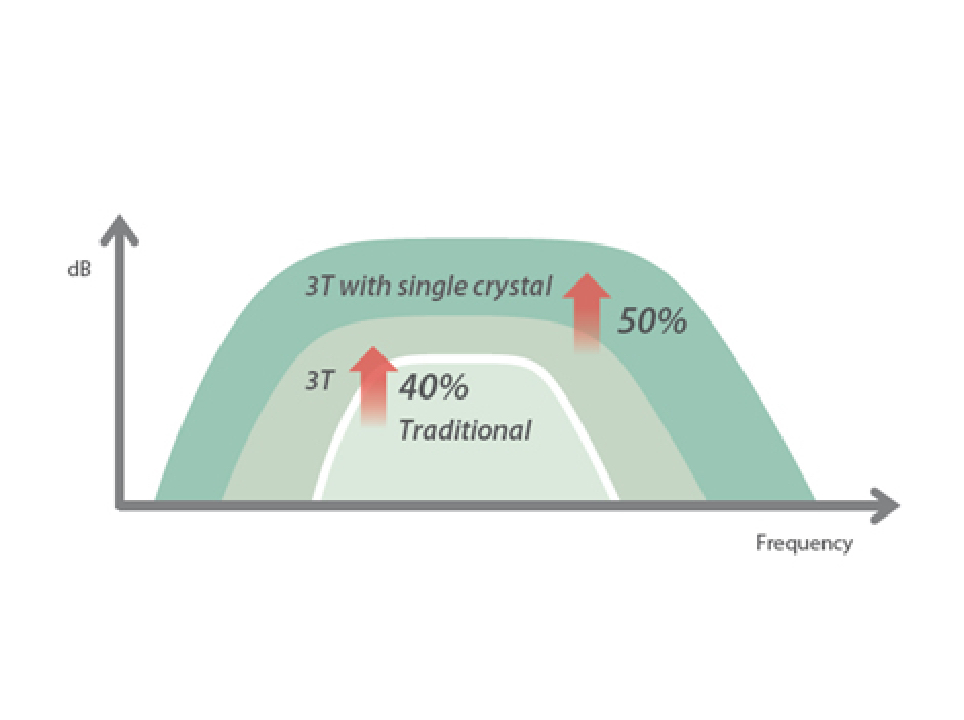

eXpress Clarity

More clarity at hand

To achieve excellent images with minimal effort is always the highest clinical priority and Mindray's endless pursuit. With continuous innovation of imaging and transducer technologies, X-Insight delivers express clarity as soon as the transducer touches the body.